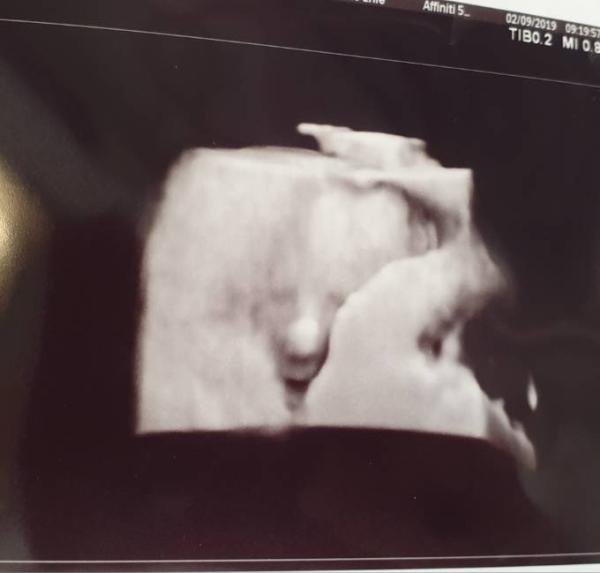

Hallo ihr Lieben, Ich melde mich mal wieder mit Bild und Neuigkeiten. Der Kleinen oder dem Kleinen (Sie war sich heute nicht mehr so sicher ) geht es prächtig! 24,5cm und 375g. Bin heute 21+0 und passt wohl alles gut Bin ganz schön verliebt in mein Murkelchen Das Bild fand ich ziemlich witzig, mit dem Kopf durch die Wand

Hallo Toll, dass alles ok bei dir ist!! Schon so groß. Ich finde, die Ärzte sollen ohnehin nur dann das Geschlecht sagen, wenn sie sich 100 % sicher sind. Sonst stiftet das nur Verwirrung. Das 3 D Bild ist echt witzig. Frage mich immer, wie das zustande kommt. LG Edith

Süß, da hat sich jemand richtig eingekuschelt